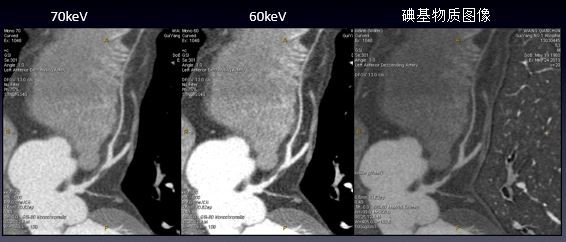

病例资料:患者男性,53岁 扫描参数 模式:GSI -60 AutomA@0.35sec/rot@DC40mm@SFOV Cardiac Large 方式:SnapShot Pulse 造影剂注射方案:350mgI/100ml@50ml@4ml/sec Cardiac GSI:LAD软斑块/远端肌桥能谱工具联合分析 1. 单能量工具:随着keV降低,VR图像血管细节显示更清楚,60keV更好的优化血管显示 2. 能谱曲线:多个感兴趣区分析,纤维斑块为主,其内见脂质髓核,且该脂质髓核靠近血管管腔,故该软斑块考虑为易损斑

3. 碘基物质图像观察:与低keV图像同样能清晰显示血管细节及软斑块内结构的密度差异